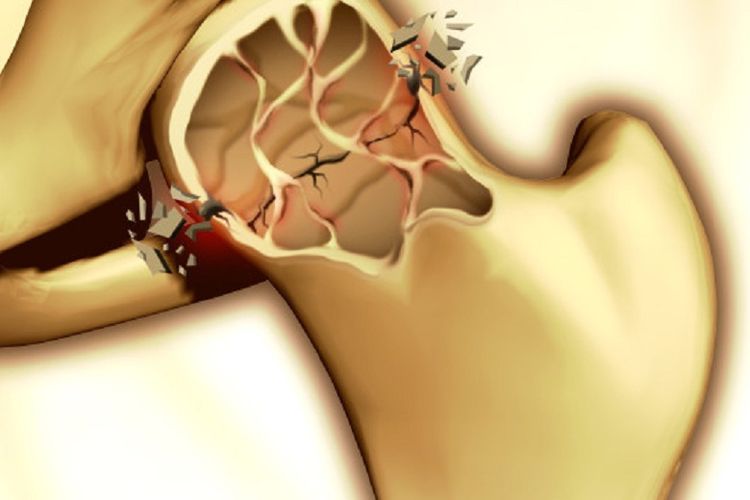

Tak perlu khawatir, karena Anda dapat memperbanyak konsumsi makanan-makanan ini untuk mencegah terjadinya osteoporosis.